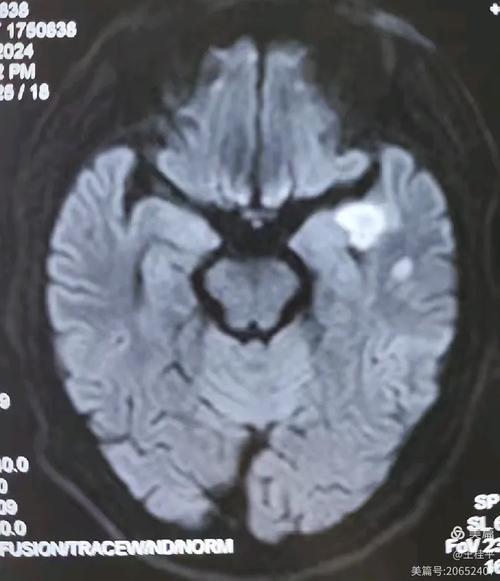

- DWI(弥散加权成像):这个序列对早期脑梗死的诊断非常敏感,但它不是导致脑梗的原因,恰恰相反,它是医生用来诊断脑梗死的工具,因为脑细胞缺血坏死后,水分子的自由运动会受到限制,在DWI图像上会显示出异常高信号,医生正是通过这个序列来发现你是否已经发生了脑梗。